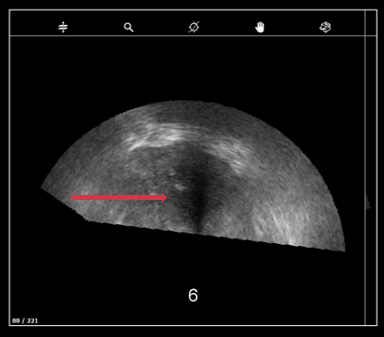

b. Incomplete prostate

- Make sure the whole prostate is included in the Panorama.

- Check if there is :

- Enough gel on the probe head

- No air bubble in the probe protection

c. US depth not well adjusted

- Adjust the prostate depth so the prostate does not take up more than half of the US image.

- When taking a panorama, make sure the prostate fits inside the yellow box.